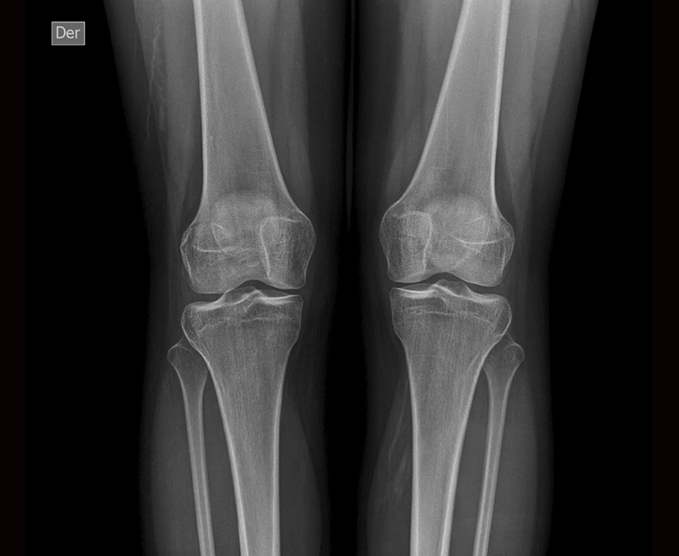

Radiología simple

Una radiografía es una prueba rápida e indolora que genera imágenes de las estructuras internas del cuerpo, en especial de los huesos.

- Rodilla